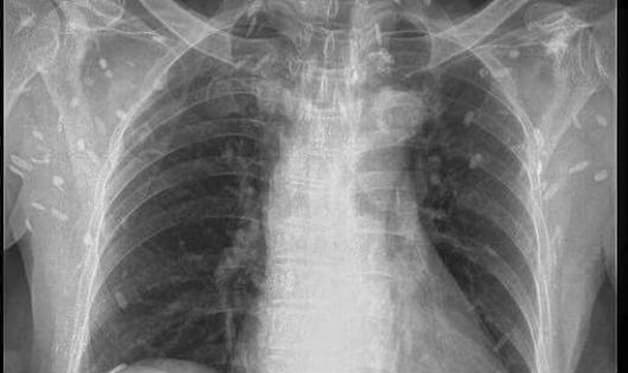

Chụp X quang là trợ thủ đắc lực trong việc điều trị và chẩn đoán các bệnh lý như là gãy xương, viêm khớp, viêm phổi và các bệnh lý liên quan đến răng miệng, tim mạch, cơ xương khớp, tiêu hóa, thần kinh. Tuy nhiên, chụp X quang lại không thích hợp để chẩn đoán những bệnh lý thuộc bộ phận các mô mềm như là gan vì hình ảnh thu lại không được rõ nét.

Chụp X quang được hoạt động bởi tia X, đây là một dạng năng lượng cao. Những chùm bức xạ tia X khi được phát ra từ máy chụp X quang có khả năng đi xuyên qua các bộ phận mô mềm, dịch trong cơ thể người một cách dễ dàng và bị cản lại bởi các mô có độ đậm đặc cao. Từ đó, thu lại được những hình ảnh phản chiếu các bộ phận trong cơ thể giúp bác sĩ dễ dàng quan sát và chẩn đoán bệnh chính xác.

– Sau khi đi xuyên qua cơ thể, chùm tia X sẽ chiếu vào máy phim hoặc máy dò đặc biệt. Các mô đặc sẽ chặn lượng bức xạ cao như là xương, răng và hiển thị dưới dạng vùng trắng trên nền đen. Các mô mềm ngăn chặn ít lượng bức xạ hơn thì phản chiếu cho ra hình ảnh màu xám. Những khối u sẽ có cấu trúc dày đặc hơn các mô xung quanh cho nên sẽ có màu xám nhạt hơn. Còn lại, các cơ quan mô mềm như phổi, gan thì sẽ cho ra hình ảnh màu đen.

Dựa vào hình ảnh được hiển thị trên màn phim chụp X quang bác sĩ có thể chẩn đoán và xác định được mức độ thương tổn của người bệnh để đưa ra phác đồ điều trị chính xác nhất.

Tia X là một dạng bức xạ truyền thẳng xuyên qua cơ thể giúp thu lại hình ảnh phản chiếu các bộ phận bên trong mà không phải trực tiếp mổ